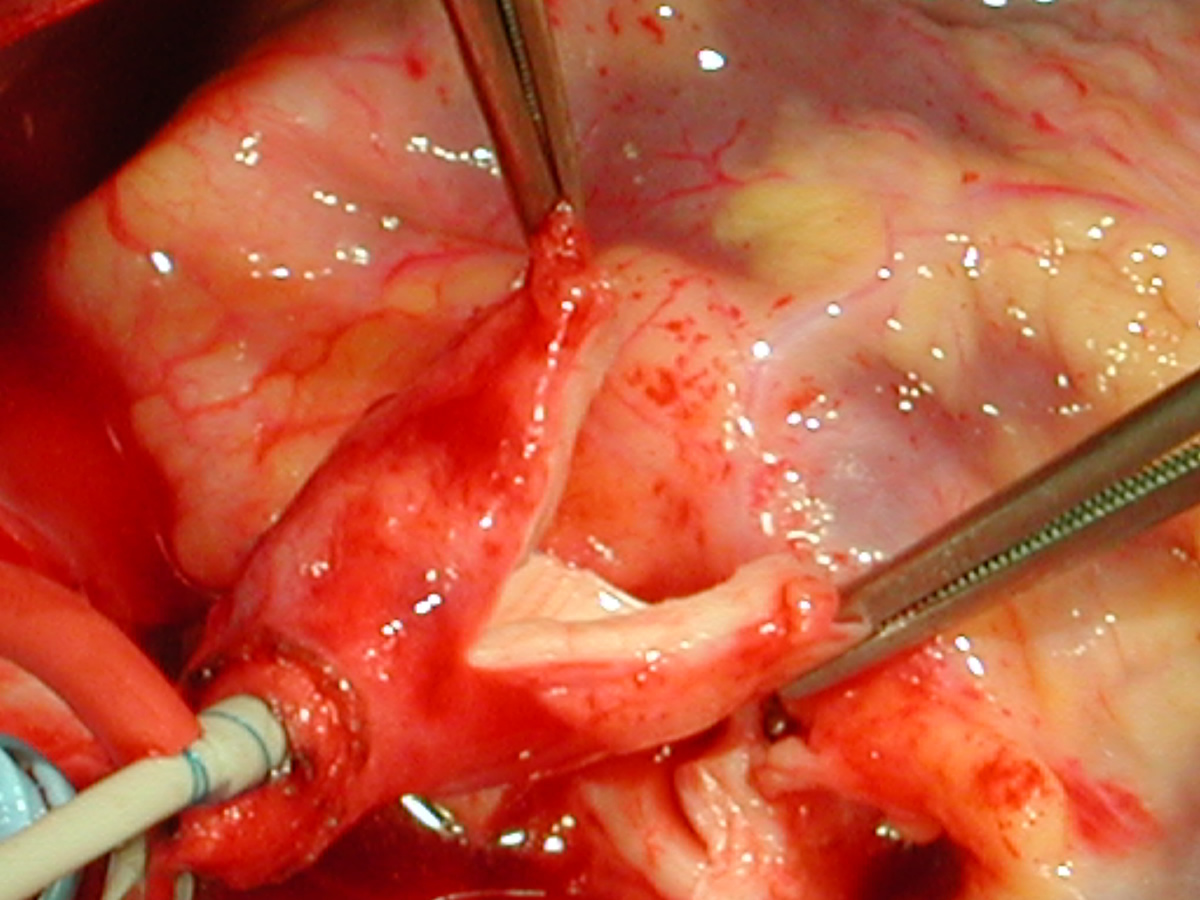

An asymptomatic, 5-year-old, 18-kg boy known by genetic testing to have Williams syndrome on physical examination had a IV/VI harsh systolic ejection murmur and no diastolic murmur. Preoperative echocardiogram showed an aortic root dimension of 2 cm and the dimension at the level of stenosis in the ascending aorta was 8 mm. Peak echocardiogram gradient was 70 mm Hg with a cardiac catheterization gradient of 50 mm Hg. The child had no peripheral pulmonary artery stenosis.

Preoperative transesophageal echocardiogram in long-axis view shows ascending aorta with aortic valve to the left. The markers indicate the aoritc root dimension to be 2.0 cm and hte mid portion of the stenosis to be 0.8 cm.